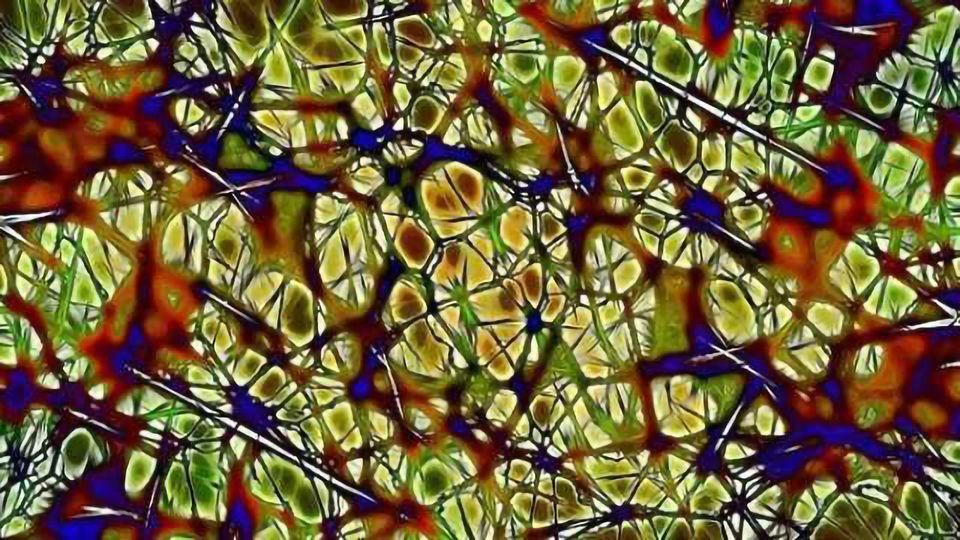

How to repair nerve damage. Clinically relevant anatomy nerve regrowth in the peripheral nervous system is dependent on the type of injury. Surgical intervention with nerve grafting is necessary to repair the injury. Surgical nerve repair involves exploration of the injured nerve and removal of injured tissue or scar from the nerve endings.

The outer epineurium is stronger than the other layers and often remains intact (unbroken). A nerve injury can affect the brain's ability to communicate with muscles and organs. However, the complex inner layers of the nerve are disrupted.

These injuries are usually found in laceration or severe stretch injuries. By amino science posted on: Peripheral nerves are fragile and easily damaged.